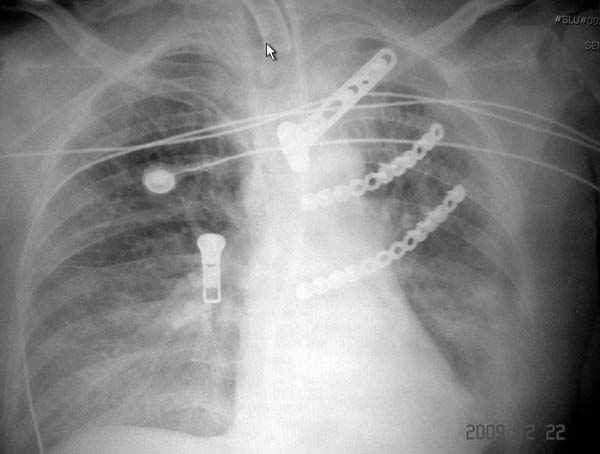

К нам поступила больная 56 лет после автоаварии в бессознательном состоянии, которая срочно заинтубирована в приемном отделении и сделаны необходимые исследования. Данные КТ и рентген показали перелом дистального бедра и Dissociation upper extremity - закрытый отрыв левой верхней конечности на уровне грудинно-ключичного сочленения и множественные переломы ребер.

На поверхности грудной клетки из-за полного разрыва грудной мышцы под кожей заметно биение сердца и след от ремня безопасности. Грудная клетка расширена из-за смещения верхней конечности вверх и латерально. Признаков васкулярного повреждения нет, и из-за отсутствия сознания не смогли определить наличия повреждения нервов.

Срочно в операционной наложен наружный фиксатор и травма хирургом поставлены трубки в плевральную полость.

На седьмые сутки нами совместно с торакальным хирургом сделана операция по фиксации грудинно-ключичного сочленения и переломов ребер.